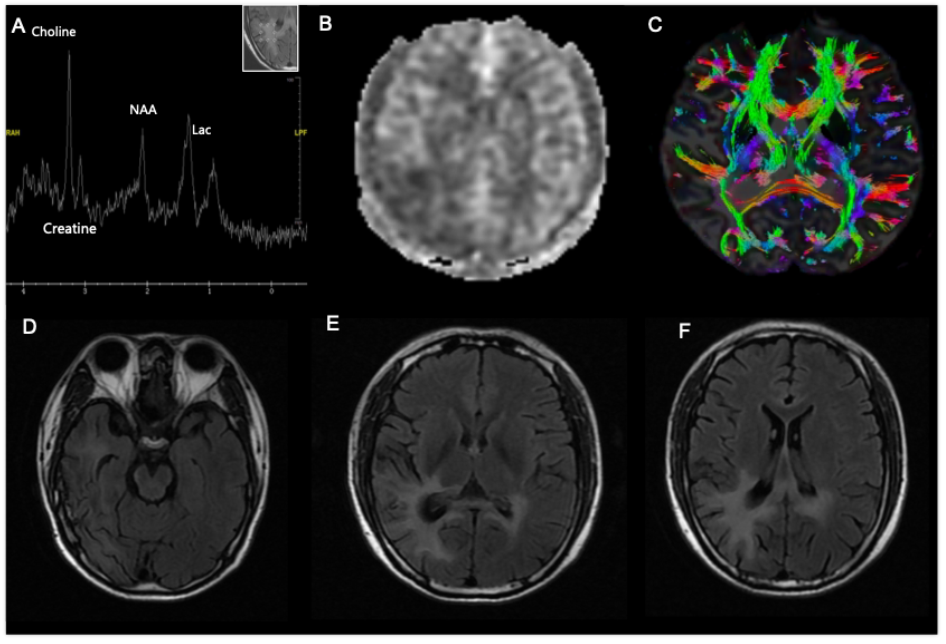

入院情况

图1 2023年6月头颅MRI结果(A~C);2024年8月头颅增强MRI结果(D~F)

3. 影像学

(3)多模态MRI

▶ASL灌注成像:病灶均低灌注。

▶MRS成像:病灶胆碱峰、乳酸峰升高,肌酸峰及N-乙酰天门冬氨酸峰下降。

▶DTI序列成像:胼胝体纤维稀疏,未见白质破坏性病变。

此后患者接受了多模态MRI检查:MRS序列示胆碱峰升高伴N-乙酰天门冬氨酸峰降低(图3A);ALS灌注成像示病灶区域低灌注(图3B);DTI序列示胼胝体压部纤维束减少、退变(图3C)。以上改变均高度提示病灶为纤维退变可能性大,不具备明显代谢活性或占位效应。因此结合患者首次脑梗死病史,综合考虑诊断脑梗死后华勒氏变性可能性大。

图3 患者多模态MRI成像及随访MRI结果